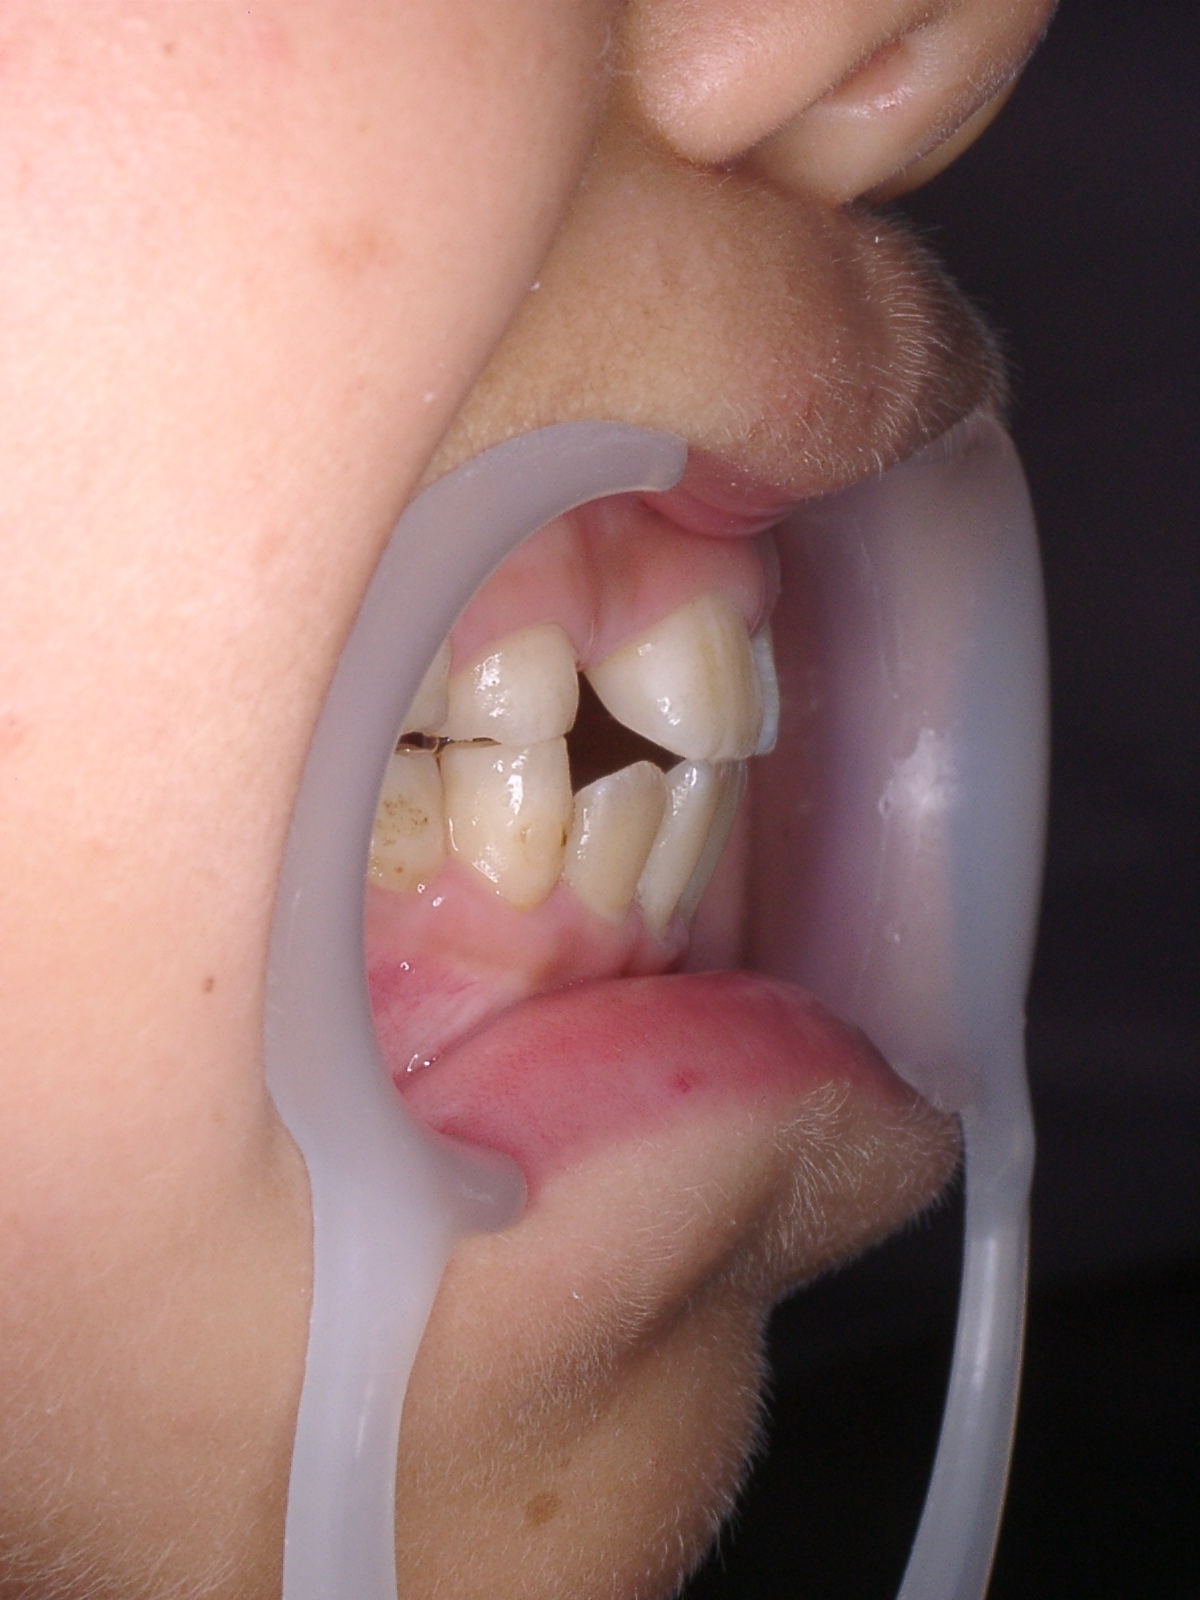

今回は、反対咬合の症例を御紹介します。

右側咬合時 術前.JPGのサムネール画像術前です。

乳歯のころから、反対咬合の傾向にありましたが

永久歯が生えるときに改善する場合もあるので

様子を見ていましたが

やはり、反対咬合になってしまいました。

右側咬合時 術後2.JPG 装置を入れて一カ月後です。

反対だった前歯の噛み合わせは治ってしまいました。

(全ての症例が、すぐに治るわけではありません)

他の歯が生える場所がないため、矯正治療は続けています。

放っておいたら、反対咬合の顔立ちになっていたと思いますので

早めに治療を開始してよかったですね。